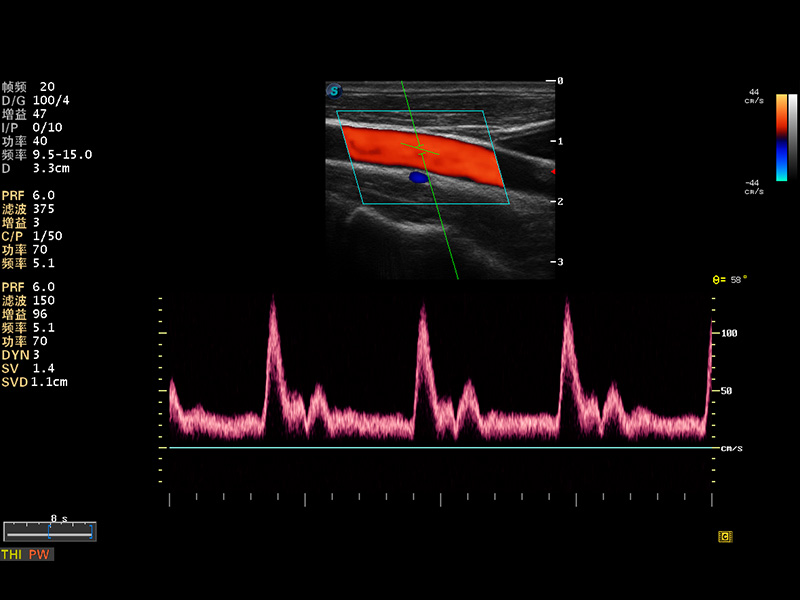

μ-Scan微米成像

谐波成像